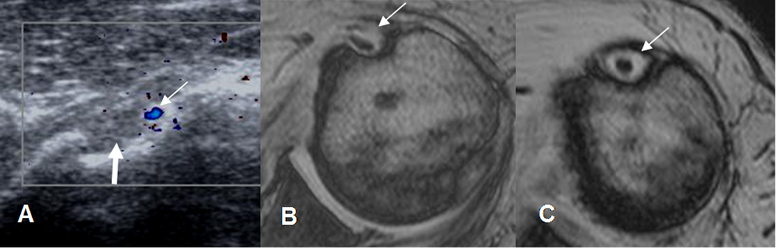

Una pequeña cantidad de líquido puede encontrarse en la parte lateral, rodeando el tendón del bíceps. (12). Corresponden a estructuras vasculares adyacentes al tendón. (Vasos circunflejos humerales anteriores). (12). (Fig 21).

Fig 21. Tendón del biceps.

A: Ecografía doppler. Vasos circunflejos (Flecha delgada), en la parte lateral de la corredera bicipital. Tendón del biceps (Flecha gruesa).

B: RM axial en FFE. Escaso líquido normal, en la parte lateral

C: RM axial en FFE. Tendón completamente rodeado por líquido, secundario a tenosinovitis.